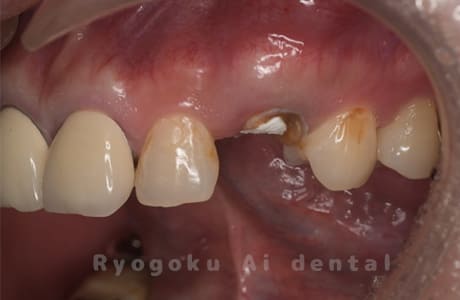

Case09

-

- 原因

- 左上6番重度カリエス

- 治療内容

- クラウンレングスニング

- 治療費用

- 44,000円(根管治療、補綴は別途費用)

他院で抜歯と判断された歯です。クラウンレングスニングを行い、保存を試みました。現在も問題なく被せ物が入り、使用できてます。

<リスク・副作用>

手術後は痛み、腫れ、痺れ、青あざなどの副作用が生じます。痛みは痛み止めを処方しますが、腫れ、青あざは1週間程度生じる場合があります。また、部位によっては神経の走行が複雑で、痺れが残り、長期的にお薬を処方する場合があります。